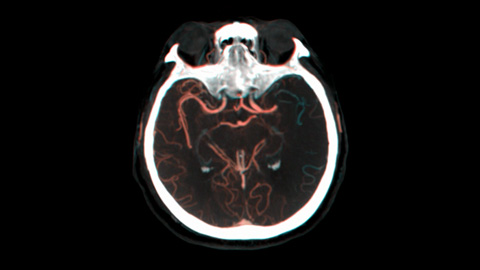

Diese moderne Doppelkontrast-Roadmap verbessert die Visualisierung überlappender Gefäße bei gleichzeitigem Management der Strahlenexposition und ermöglicht so informierte Entscheidungen, ob und wie das Gerinnsel erreicht werden kann.

Diese moderne Doppelkontrast-Roadmap verbessert die Visualisierung überlappender Gefäße bei gleichzeitigem Management der Strahlenexposition. Sie kann individuell angepasst werden, um das Vordringen beim Platzieren des Coils sichtbar zu machen.